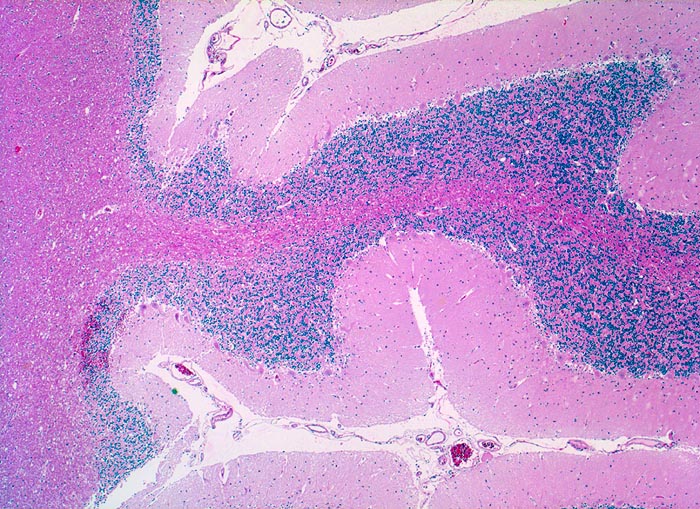

Wegen der hohen Zelldichte und der hohen Kern-Zytoplasmarelation erscheinen die Tumoren in der HE Färbung blau. Medulloblastome müssen differentialdiagnostisch von morphologisch ähnlichen kleinzelligen undifferenzierten Karzinomen und Lymphomen abgegrenzt werden. Das klassische Medulloblastom besteht aus dicht gepackten Zellen mit runden bis ovalen oder karottenförmigen stark hyperchromatischen Kernen umgeben von wenig Zytoplasma. Runde Zellen mit weniger dichtem Chromatin sind oft beigemischt. Zahlreiche Mitosen, flächenhafte Nekrosen und Apoptosen sind typisch. In weniger als einem Drittel der Fälle findet man die typischen Homer-Wright Rosetten. Diese bestehen aus ringförmig angeordneten Tumorzellkernen um ein fibrilläres Zentrum aus Zytoplasmafortsätzen.

• Scharf begrenzter rundlicher sehr zellreicher (deshalb blauer) Tumor.

• Monomorpher Zellrasen mit hyperchromatischen ovalen oder karottenförmigen Zellkernen.

• Kaum erkennbares Zytoplasma.

• Homer-Wright Rosetten aus ringförmig angeordneten Tumorzellkernen um ein fibrilläres Zentrum aus Zytoplasmafortsätzen.